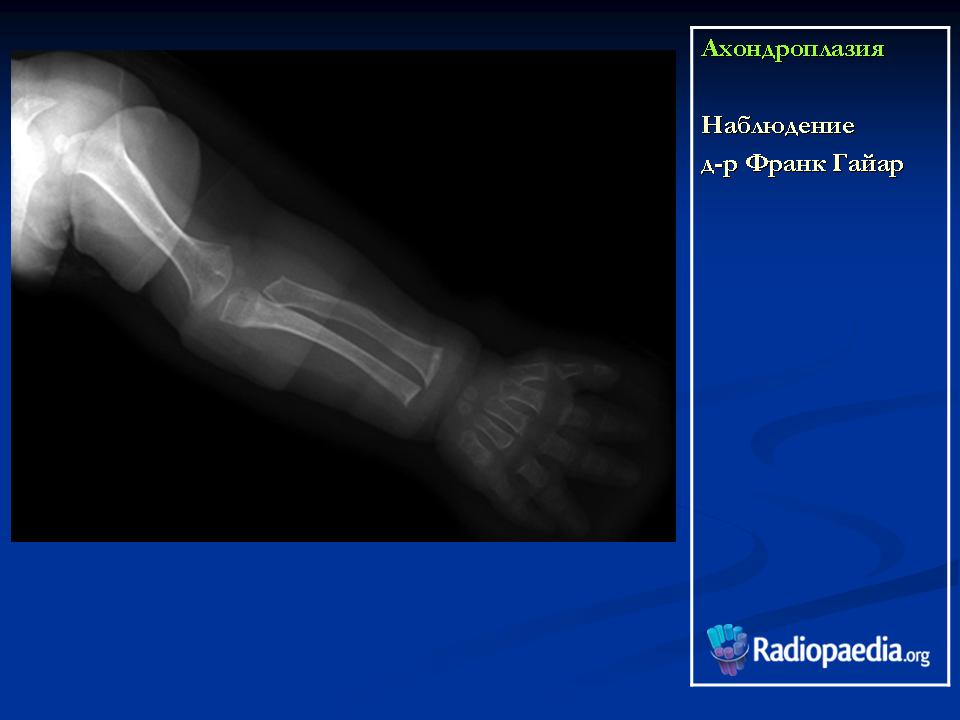

Наблюдение д-ра Франк Гайар

Характерными признаками гетерозиготной ахондроплазии являются укорочение конечностей, поясничный лордоз, короткие пальцы, макроцефалия с выступающим лбом и запавшей переносицей. Трубчатые кости, как правило, сохраняют правильную форму. Их деформация встречается не более чем в 25-30% наблюдений. Грудная клетка и живот не отстают от нормативных для срока значений.